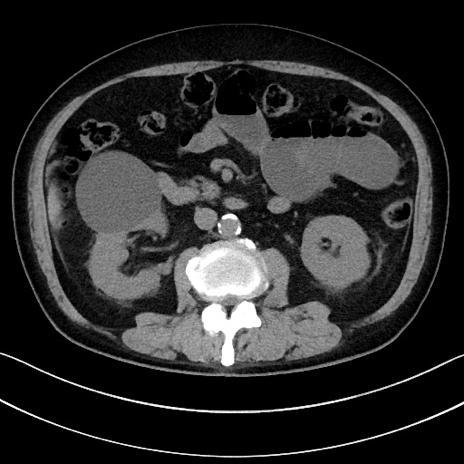

症例15(横断像)

【症例】70歳代男性

【主訴】腹痛

【現病歴】今朝から腹痛あり。全体的に痛い。特に左上の方。排ガスが今日はない。冷や汗が出る。

【既往歴】直腸癌術後

【身体所見】左側腹部〜上腹部に圧痛あり。腹膜刺激症状明らかなではない。軽度反跳痛。左下腹部に術後瘢痕あり。

【データ】WBC 7700、CRP 0.02